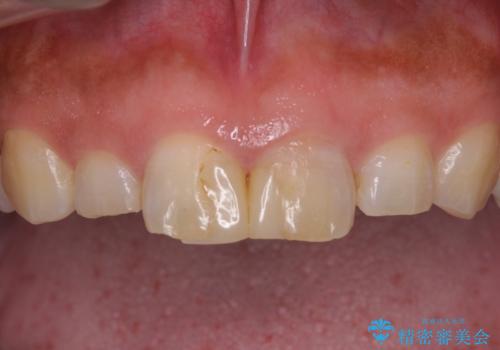

- 前歯の形と色を気にして来院された患者様です。

虫歯で神経を取り除いたことによる変色や充填物の着色などが認められたため、オールセラミッククラウンにて補綴することとしました。

また、咬耗により周囲の歯がすり減ったことで、前歯2本のみが長く見えていたため、周囲に長さを合わせることとしました。